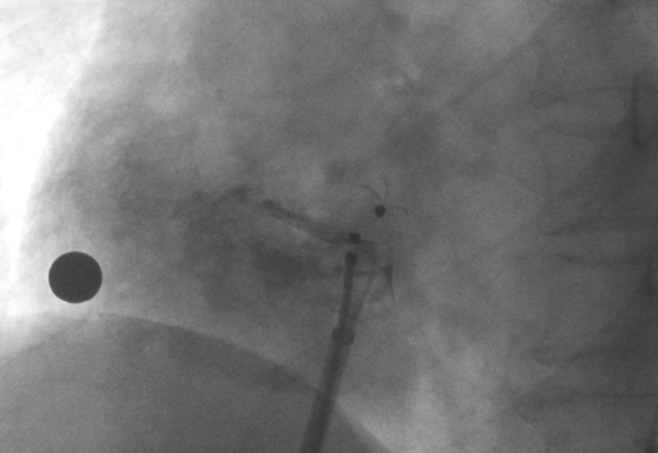

造影顯示PFO封堵完全,無殘余分流, 試驗(yàn)器械充分舒展并貼合良好

術(shù)中造影顯示患者為PFO且長隧道型,目前市場上已商業(yè)化的PFO封堵器難以滿足該患者解剖結(jié)構(gòu)封堵需求。迪創(chuàng)醫(yī)療自主研發(fā)的OmniSeal PFO封堵器自適應(yīng)性雙盤貼合設(shè)計(jì)能廣泛適應(yīng)不同PFO隧道長度的解剖結(jié)構(gòu)和形態(tài),其雙盤外包覆式阻流和隧道內(nèi)填充阻流相結(jié)合的雙重阻流設(shè)計(jì),可為此患者實(shí)現(xiàn)有效封堵。與此同時,OmniSeal首創(chuàng)的完全可穿刺式設(shè)計(jì),也為此患者最大程度地保留了房間隔區(qū)域穿刺通道,以實(shí)現(xiàn)全兼容未來可能的左心系統(tǒng)二次介入術(shù)。術(shù)終造影和心臟超聲顯示封堵完全、效果良好。作為OmniSeal的首例臨床應(yīng)用,本次手術(shù)的順利完成和優(yōu)異效果充分體現(xiàn)了產(chǎn)品的設(shè)計(jì)創(chuàng)新優(yōu)勢。